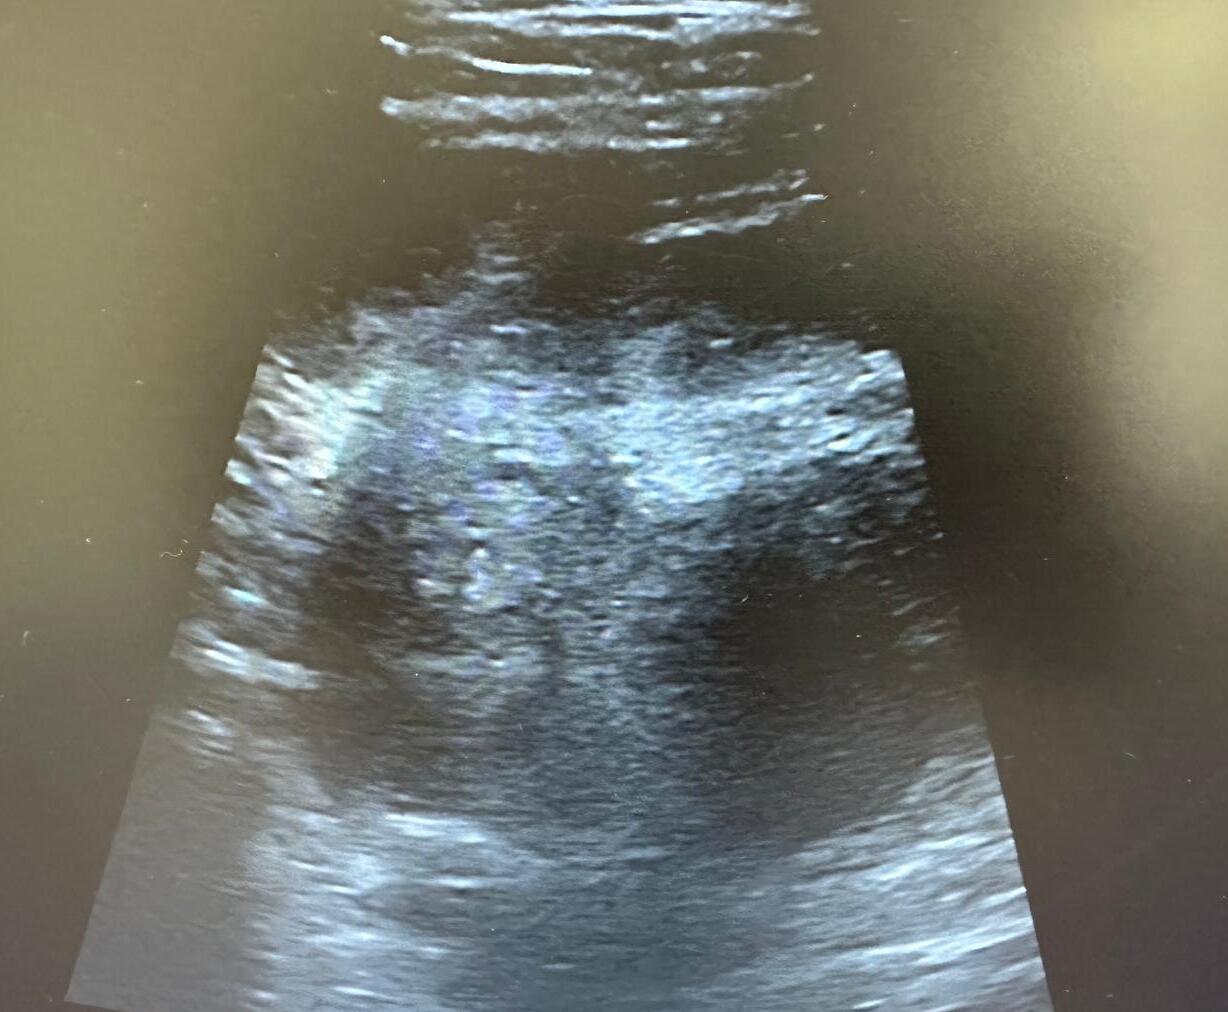

A nivel ecográfico se visualiza imagen profunda, heterogénea, de márgenes poco definidos, sin captación Doppler, más profunda que el margen del glúteo medio.